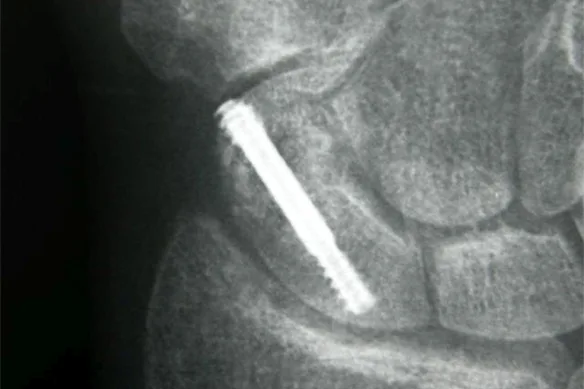

είναι να χειρουργούνται, εκτός εάν συντρέχουν λόγοι που αποτρέπουν αυτή την απόφαση. Χρησιμοποείται

μία ειδικά σχεδιασμένη βίδα ή 2 βελόνες. Με τον τρόπο αυτό αποφεύγεται η χρήση γύψου, ο ασθενής

επιστρέφει ταχύτερα στην εργασία του και οι επιπλοκές περιορίζονται σημαντικά.